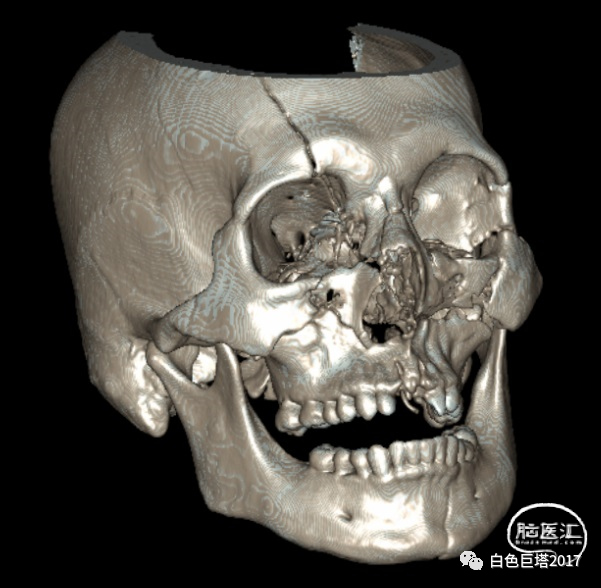

患者苏某,34岁男性,因“高处坠落致意识障碍1小时余”入院。患者自8米高处坠落,头面部着地,入院时头面创口、口腔、鼻腔流血不止,GCS E2V1M5为8分。很快出现血压下降至70/52mmHg、血氧下降85%。急诊气管插管,完善头颅、颈椎、胸腹部CT检查,提示颌面、颅底多发骨折、鼻腔积血,软组织挫裂伤,左颞颌关节脱位,牙齿缺失。额骨骨折、右额顶叶脑挫裂伤、蛛网膜下腔出血,颅内积气。颈椎间盘突出、颈椎退行性变、未见明显骨折。双侧1-2肋骨骨折,T5-7左侧横突骨折;双肺挫伤;左侧少量气胸。腹腔脏器未见明显损伤表现。